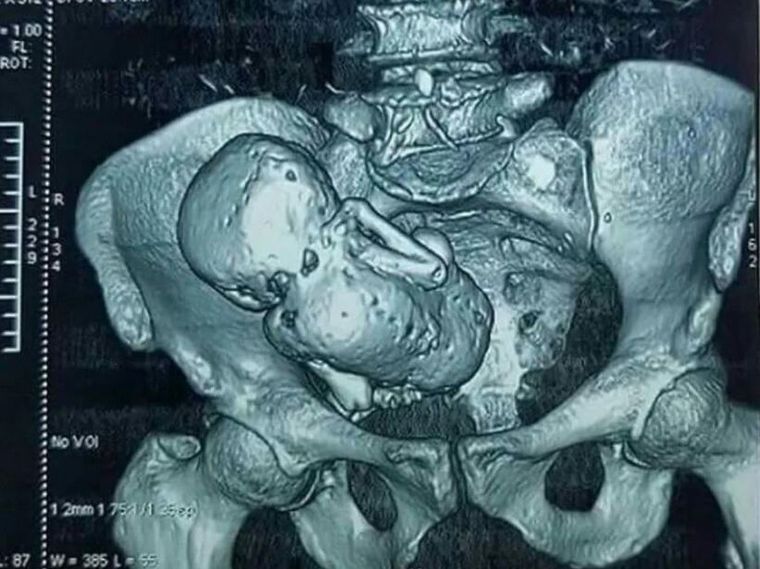

Se trata de un feto con 40 semanas de gestación, el cual se “momificó” en el interior del vientre de la madre luego de que se detuviera su desarrollo como en un embarazo normal.

Para la medicina, se trataría de un caso de litopedia, un proceso que se genera cuando un óvulo fertilizado se adhiere a un lugar fuera del útero. Aunque el feto comienza a crecer, no puede sobrevivir por no encontrarse en el lugar y las condiciones adecuadas.

El cuerpo humano identifica al feto como un objeto extraño y empieza a protegerse envolviéndolo con calcio, lo que explicaría la “momificación”.

La medicina solo ha registrado 300 casos de litopedia en toda la historia.